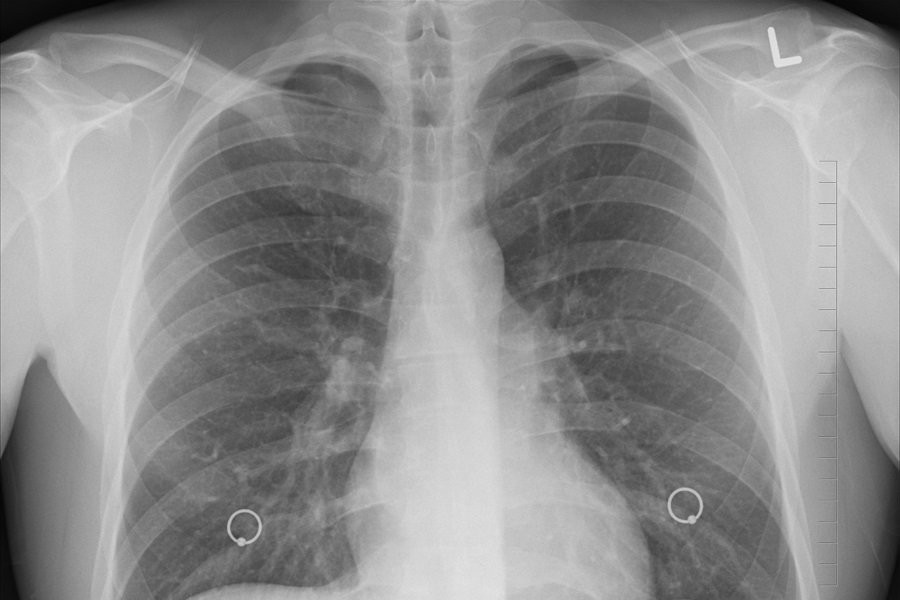

Она позволяет проводить анализ компьютерных томографий и обнаруживать признаки 7 различных патологий, включая опухоли, коронавирус, травмы позвоночника, жидкость в плевральных областях, ишемическую болезнь сердца, аневризму аорты и расширение легочного ствола.